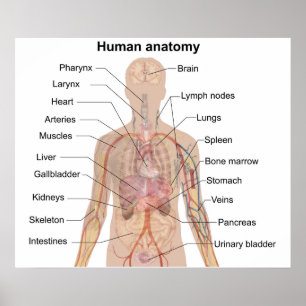

Anatomi i mänskliga organ vykort

Pris23,00 kr

Anatomi i mänskliga organ poster

Pris229,00 kr

Anatomi i mänskliga organ canvastryck

Pris1 425,00 kr

Anatomi i mänskliga organ hälsningskort

Försäljningspris 49,00 kr. Ursprungligt pris 54,00 kr.